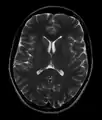

![]() Cross-sectional T1-weighted MRI of a healthy human brain acquired with an ultra high-field MR of 7 Tesla field strength | |

- T2-weighted (T2W) images: CSF is light, but fat (and thus white matter) is darker than with T1. T2-weighted images are useful for visualizing pathology.[26]